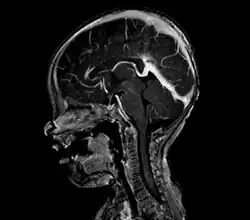

Large arteriovenous malformation of the parietal lobe